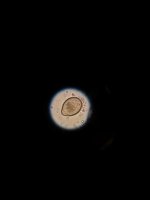

Hello everyone, I apologize for this being my first post ever here and not properly introducing myself but I promise I will shortly. Anyways here's the story on this gecko: I came across her on craigslist being sold as a mack snow leopard gecko, she was skinny and beat up by her leopard gecko tank mate. I decided to take her in and set her up in a quarantine tank on paper towels, precautionary dewormer with panacur for three days and hand/syringe fed food. She had some runny feces for awhile that went away with time. She then gained 5 grams but then the runny feces came back and she's lost weight since it began again. Noticing the change I did a direct smear on her and found a few parasitic eggs I need help to ID. I believe one is a pinworm egg and read that's part of normal gut flora and shouldn't be of too huge of a concern. Didn't find more than two pinworm looking eggs (under 40X) and one round unknown egg 40X). The last slide I was looking under Oil Immersion 100X I found ghostly looking oocysts... professor said Crypto. I'm fearing the worst and getting her tested asap but I would like opinions on my findings please..